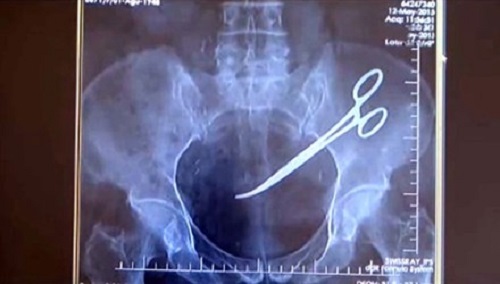

Bỏ quên kéo trong bụng bệnh nhân

Tháng 11/2015, bà Hanim (Thổ Nhĩ Kỳ) phát hiện những cơn đau bụng và dạ dày liên tục. Bà đã đến bác sĩ để thăm khám nhằm xác định nguyên nhân. Qua phim chụp X quang, các bác sĩ nhận thấy có một dị vật ở bụng, gây viêm nhiễm nặng toàn bộ khu vực ổ bụng.

Thấy tình hình khẩn cấp, các bác sĩ đã tiến hành phẫu thuật lấy dị vật ra khỏi bụng bà. Dị vật được xác định là cái kéo phẫu thuật đã bị bỏ lại bên trong.

Được biết, trước đó, bà từng trải qua quá trình phẫu thuật để cắt bỏ ung thư cổ tử cung. Ca phẫu thuật được xem là thành công nhưng về sau những cơn đau ở bụng liên tục xuất hiện. Dù lo lắng nhưng khi nghe bác sĩ nói đó là đau hậu phẫu nên bà không mấy lo lắng.

Sau sự việc trên, bà Hanim đã đệ đơn kiện bệnh viện và đòi bồi thường cho những đau đớn đã phải trải qua suốt 5 năm.